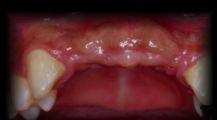

CASE 3

CASE 4

CASE 5

CASE 6